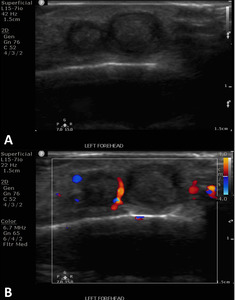

The patient is a 25-year-old male who was struck by a paintball in the left frontotemporal region, initially causing bleeding and ecchymosis. Two months later, he presented to an outpatient vascular clinic due to the development of a pulsatile mass of the left forehead (Figure 1). The clinical finding prompted a diagnostic US including arterial duplex evaluation of the site which confirmed tandem pseudoaneurysms in the scalp left of midline arising from the parent left superficial temporal artery (Figure 2).

After discussion and counseling regarding the treatment options, the patient elected to have the percutaneous procedure performed in lieu of surgery as his initial choice of treatment. The patient emphasized understanding that a surgical excision may be required in the future for complete cosmetic and symptomatic resolution. Two weeks after the ultrasound study was conducted, the pseudoaneurysms were treated with direct, percutaneous pseudoaneurysm needle access and subsequent angiogram and n-BCA glue embolization. Specific procedure details include: the procedure was performed under moderate sedation with IV administration of midazolam and fentanyl. The forehead was prepped and draped in sterile fashion and subcutaneous injection of 1% lidocaine was used for local anesthesia. Then, the pseudoaneurysm was percutaneously accessed with a 21-gauge needle under direct US guidance. Angiography through the needle demonstrated successful access to the pseudoaneurysm; which was located at a branch point of the STA. Further angiographic opacification of the vascular territory demonstrated two additional small pseuaneurysms, one arising from each branch (Figure 3).